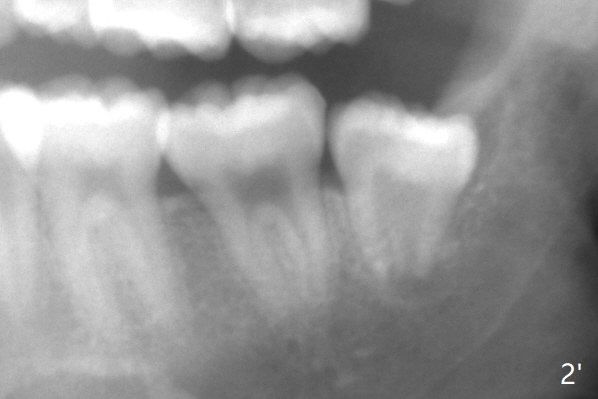

A 19-year-old man with history of orthodontic treatment (Fig.1,2) returns to office for #1,16,17,32 extraction with Collagen Plug placement at #17 and 32 (4-0 plain gut suture). The sockets heal in 4.5 months (Fig.3).